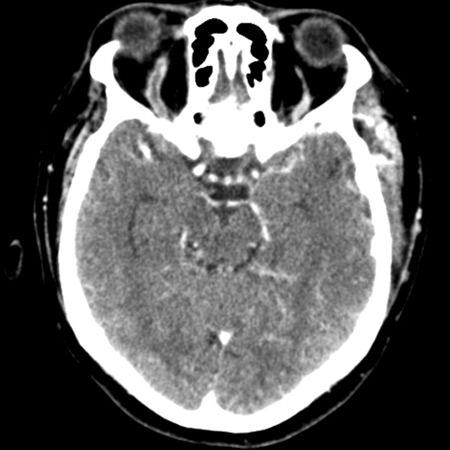

A TC e a RNM cranioencefálicas são as principais modalidades radiológicas usadas para confirmar o diagnóstico em todos os pacientes, e também são usadas para avaliar patologias causais e concomitantes.[43][52]​​​ Nenhuma das duas é absolutamente sensível ou específica para o diagnóstico de trombose do seio cavernoso (TSC). Uma TC com contraste é considerada superior à RNM para a detecção da formação inicial de coágulos nos seios cavernosos, enquanto a RNM é superior para o restante dos seios venosos durais.[55]​​

A TC é realizada idealmente pelo uso de uma técnica de escaneamento dinâmico com uma injeção em bolus e infusão contínua de contraste e uma varredura a intervalos seccionais próximos (menos de 3 mm) e em secções coronais e axiais.[63]

Extensões angiográficas da TC também podem ser realizadas.[Figure caption and citation for the preceding image starts]: Tomografia computadorizada (TC) sagital de crânio revelando uma veia oftálmica superior direita tubular aumentadaJones RG, Arnold B. Sudden onset proptosis secondary to cavernous sinus thrombosis from underlying mandibular dental infection. BMJ Case Rep. 2009;2009. pii: bcr03.2009.1671. Usado com permissão [Citation ends].com.bmj.content.model.Caption@5f487de6[Figure caption and citation for the preceding image starts]: Tomografia computadorizada (TC) de crânio na fase pós-contraste venosa (visão axial) revelando uma veia oftálmica superior direita aumentada em forma de "S" associada a proptoseJones RG, Arnold B. Sudden onset proptosis secondary to cavernous sinus thrombosis from underlying mandibular dental infection. BMJ Case Rep. 2009;2009. pii: bcr03.2009.1671. Usado com permissão [Citation ends].com.bmj.content.model.Caption@1799986a A venografia por TC também pode ser útil para confirmar o diagnóstico nos pacientes com suspeita de TSC.[52][53][54]​​